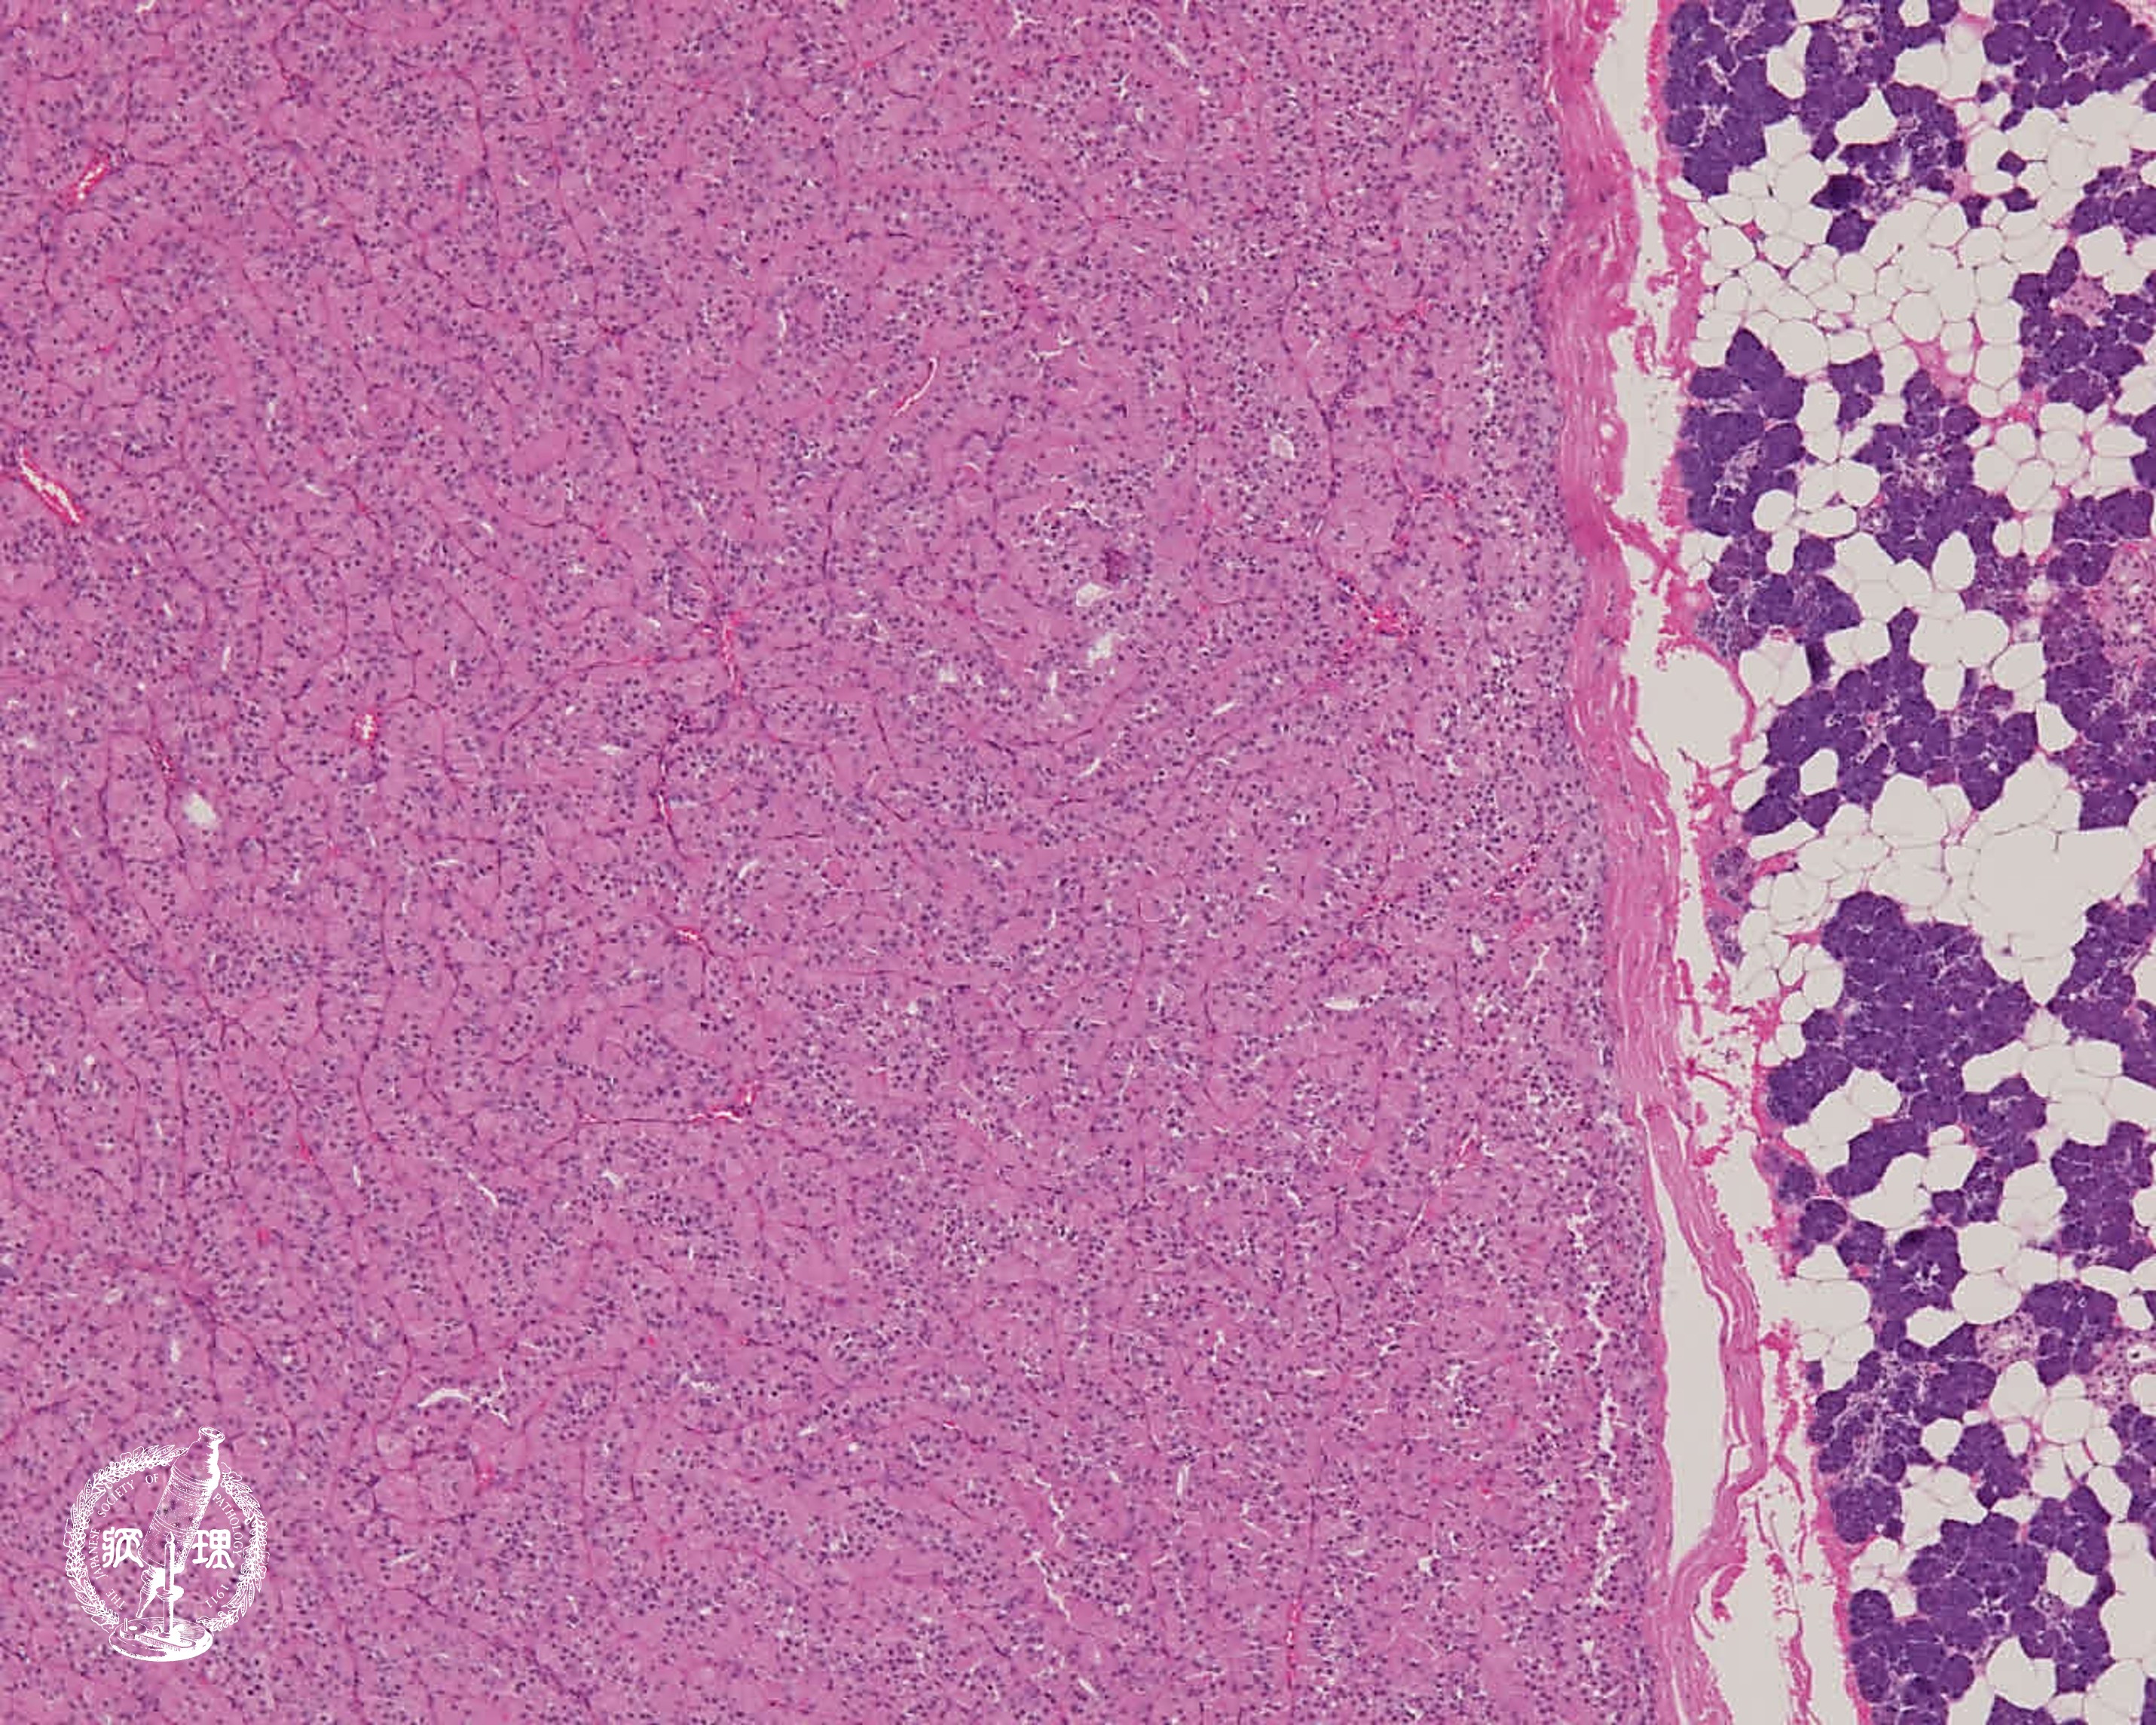

マクロ像:境界明瞭な黄褐色充実性腫瘤であり、一部に嚢胞性変化を伴う。

• 唾液腺腫瘍 (オンコサイトーマ)